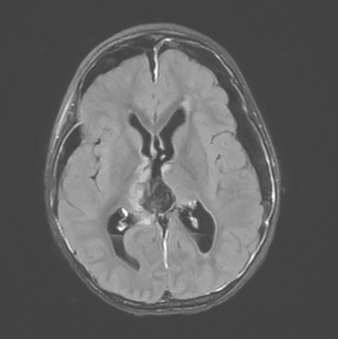

患者女,4岁6月,症状为双上肢震颤、右侧踝阵挛。院外头颅MRI平扫示松果体区占位性病变并梗阻性积水、间质性脑水肿。在上海儿童医学中心张江院区神经外科进一步行头颅MRI平扫+增强检查,于松果体区见团块样占位,大小约29.4*26.7*26.5mm,T1WI低信号,T2WI稍高信号,有明显不均匀强化。影像学诊断为右侧丘脑至松果体区占位,考虑恶性肿瘤。

患儿术前MRI图像